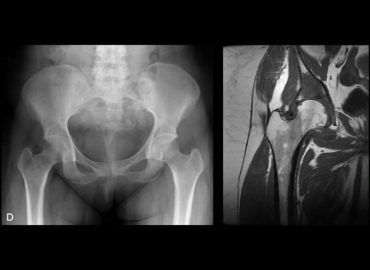

Mujer de 28 años con coxalgia derecha progresiva de un año de evolución.